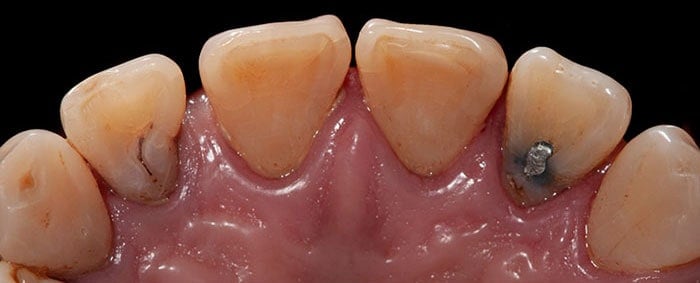

Las manchas dentales pueden tener diversos orígenes: intrínsecas (internas) y extrínsecas (externas) y pueden tener distintos tamaños, formas, coloración y localización.

Extrínsecas: En este caso hay que hablar de diversos alimentos tales como el café, vino, jugo de frutas, de igual forma que sucede con el habito de tabaco, pastas dentales con carbón activo y finalmente no olvidarnos de una mala higiene.

Intrínsecas: Estas puede ser causadas por una amplia variedad de diversos factores, tales como la genética, edad, medicamentos, ambientales y/o accidentes dentales. Siendo los antibióticos que contienen tetraciclinas consumidos durante el embarazo y en pacientes infantiles en etapas de crecimiento uno de los mejores ejemplos, así mismo el exceso de cantidades de fluoruro en el agua, dando origen a lo que se le conoce como fluorosis dental en donde se aprecian grandes manchas marrones en la superficie del diente

Otras casusas son: Caries, Dientes con Tratamiento de conductos, Fracturas dentales y Hipersensibilidad dental.